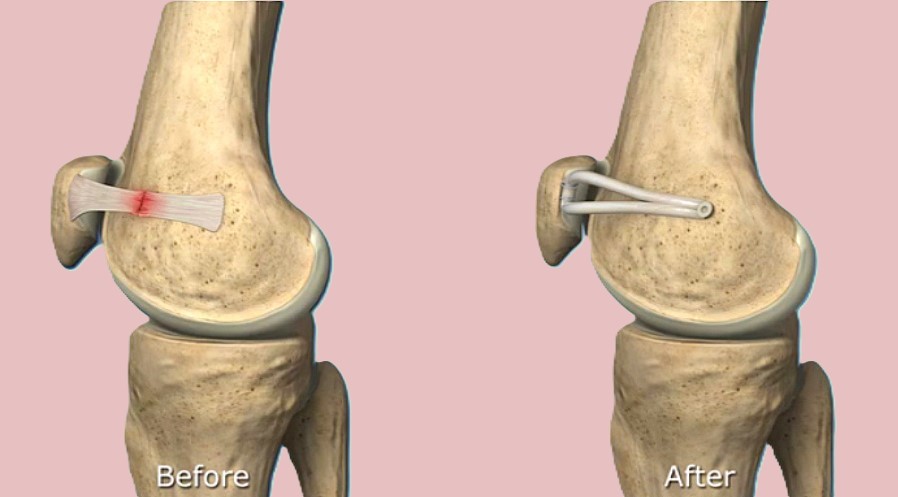

膝蓋骨脱臼

横浜整形外科クリニック野村医師は膝蓋骨脱臼に重要な内側膝蓋大腿(MPFL)靱帯を発見し解剖の教科書に書かれていなかったMPFL靱帯を1990年に世界で初めて発表しました。

その後膝蓋骨脱臼に対するMPFL再建術を開発し長年にわたり国内外で研究発表をしてきました。現在野村医師の研究したMPFL再建術は世界的に広く行われています。

膝蓋骨脱臼は軽い例から重度の例まで症例により大きな違いがあるため、安易に手術を行うと結果に大きな差が出てきます。従って術前に十分検討する必要性があります。

また初回脱臼後長い間経過すると軟骨障害がひどくなるため早めに手術する必要があります。本手術は野村医師の治療をお薦めします。

膝蓋骨脱臼の概説

横浜整形外科クリニック野村院長は30年以上にわたり膝蓋骨脱臼について研究してきました。

1990年に世界で最も早くに内側膝蓋大腿靱帯(medial patellofemoral ligament:MPFL)を発見し解剖学的研究を発表しました。MPFL再建術も世界で最初に報告しています。それ以来国内外で100以上の学会発表や和文英文論文を発表してきました。

1999年に『膝蓋骨脱臼における内側膝蓋大腿靱帯再建術損傷形態』によりSICOT国際学会賞を受賞しました。2000年以後世界的にMPFL再建術の研究が進み、2005年以後はMPFL再建術は世界の標準的手術となりました。

現在までに野村医師の膝蓋骨脱臼手術例は500例以上になり世界一です。野村医師は膝蓋骨脱臼における世界的権威です。

膝蓋骨脱臼治療の歴史

反復性膝蓋骨脱臼の治療は1950~1990年代まで、外側解離術・内側広筋前進術/内側縫縮術・脛骨粗面移行術が主な手術法(過去の手術)でした。

初回膝蓋骨脱臼の治療は関節内血腫を除去しギプスや副木固定を行うのが主体でした。しかし『どの損傷に固定が必要なのか』の基本的疑問さえ明確な答えがないまま治療が行われてきました。

ギプスの治療で十分であるとした過去の治療法が平均13年もの長期的研究(Maenpaa1997)により疑問が呈されました。初回膝蓋骨脱臼の保存的治療で満足できたのはわずかに33%のみでした。

長期的成績が多く報告されるようになり成績の不安定さとともに多くの問題がわかってきました。膝蓋骨脱臼の手術法が100種類以上もあることは裏を返せば、この疾患の本質がわからなかったことを示すものだったのです。

野村医師は日本および世界で最も早くの1990年にこの手術法を開発報告し、2000年頃より世界でこの手術法が急速に広まり、2005年からは世界の標準的手術となっています。

野村医師は世界で最も長期の報告も行い内側膝蓋大腿靱帯の安全性と有用性を立証しました。

世界的雑誌AJSMのSystematic review(Buckens 2010,AJSM)によると、MPFL再建術の2009年以前の世界の論文から信頼できる論文は12個のみでありその内野村医師は2000年に世界で最初に信頼できる論文を発表し12個の内3個の野村医師の論文が選ばれています。

野村医師は日本のほぼ全ての教科書の反復性膝蓋骨脱臼項目について執筆しており、世界的権威となっています。

内側膝蓋大腿靱帯(MPFL)再建術

横浜整形外科野村院長は世界で最も早く膝蓋骨脱臼に対するMPFL再建術を開発し現在まで500例以上の手術を行ってきました。この数は世界トップクラスです。

再建材料として1997年まで人工靭帯法、1998年に自家腱法を開発しました。手術結果は世界的雑誌 The Knee、Arthroscopy、AJSMに4つ論文が掲載されました。採取する腱の半腱様筋腱や薄筋腱は採取しても運動機能に影響はありません。人工靱帯法でも組織学的に良好な靱帯が再生されることが判明しています。世界的雑誌AJSMのレビュー(Bucken 2010,AJSM)ではMPFL再建術の2009年以前の世界の論文から信頼できる論文は12個のみであり、その内野村医師は2000年に世界で最初に信頼できる論文を発表したと記載されています。12個の内3個の野村医師の論文が選ばれています。

2022年最新手術法開発

術後スケジュールは手術2~4日目に杖なしで退院・術後リハビリ通院不要・ランニング2ヶ月~、スポーツ3ヶ月~。世界で最も早いリハビリを達成。

膝蓋骨脱臼の進行や軟骨障害

膝蓋骨脱臼で初回脱臼後10年以上になると、脱臼力も強くなり軟骨の障害例が多くなります。軟骨障害が進むと元通りに回復させることは難しく脱臼は治っても軟骨の痛みが残りますので早めに手術を受けて下さい。初回の脱臼の平均は14~18歳頃ですので手術せずに30歳代になるとこのような状態になります。